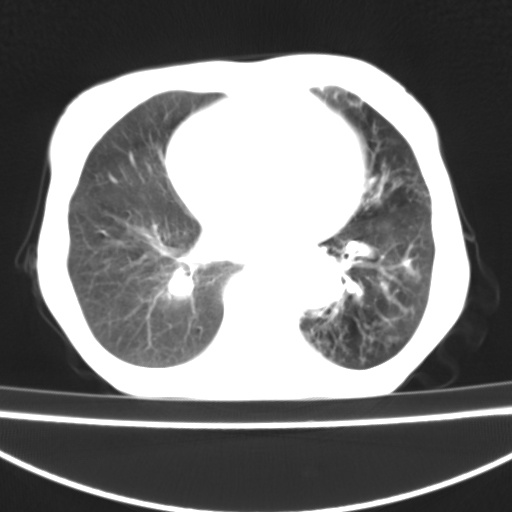

患者 女 67岁,反复咳嗽咳痰2年,加重伴喘及双下肢浮肿1月

诸大血管及f肺门血管增粗迂曲.左下肺多发薄壁空腔影.部分非也透亮度增高.薄曾扫描可区分肺气肿类型.考虑1.慢性支气管炎 2.左下肺支气管扩张 3.肺气肿 4 肺动脉高压5.是否有先心病病史

考虑1.慢性支气管炎 2.左下肺支气管扩张 3.肺气肿 4 肺动脉高压

慢支炎、肺气肿、双肺感染、左下囊状支扩。

慢支、肺气肿、肺动脉高压;左下肺囊状支扩并粘液栓形成。